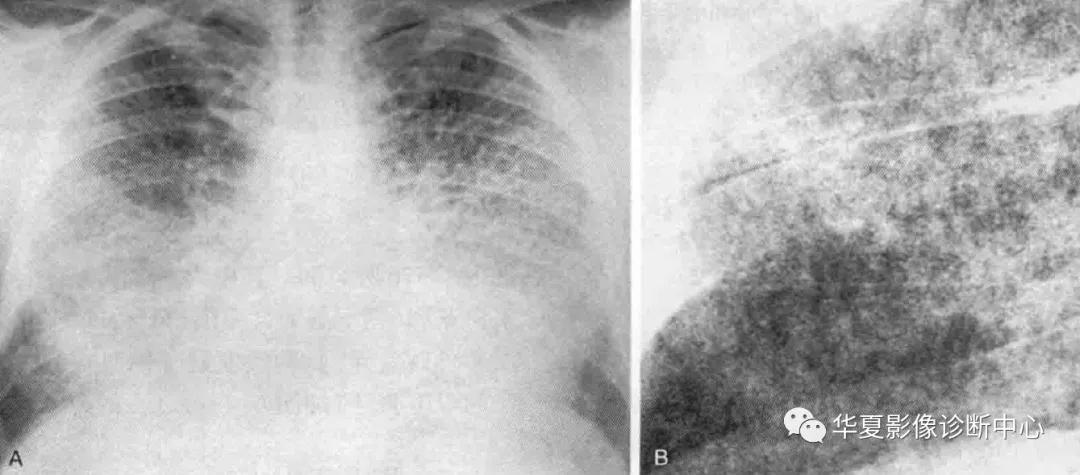

影像学表现:X线典型表现是细沙样微结节(沙尘肺),弥漫结节倾向于肺中下野更严重,有时可见网格状改变或间隔线叠加在典型的沙尘样表现上,其他表现可包括肺尖肺大泡、肺实质和肋骨间的高透亮线(胸膜黑线)、胸膜钙化。CT表现包括直径1mm或小于1mm微小钙化结节,有时融合,主要沿心缘和下肺背侧部分分布,俯卧位扫描肺的背侧持续出现更高密度;其他常见表现包括磨玻璃影、小叶间隔增厚并伴明显广泛的钙化、膈胸膜下间质增厚、间隔旁型肺气肿。